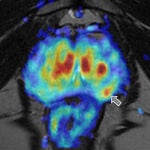

Los avances científicos en este tipo de tumor son constantes, lo que ha permitido lograr un buen pronóstico de vida para los afectados. En este camino, el último hallazgo se ha publicado hoy en la revista científica «The Journal of Urology», ya que un ensayo clínico preliminar concluye que la adición de apalutamida, un agente hormonal, puede reducir la tasa de biopsias positivas durante el seguimiento de los hombres con cáncer de próstata en estadio inicial sometidos a vigilancia activa, lo que podría ralentizar el tumor.

En el estudio, realizado por investigadores de la Universidad de Washington y el Centro Oncológico Fred Hutchinson de Seattle (Estados Unidos), el 59 por ciento de los varones que recibieron 90 días de tratamiento con apalutamida no presentaban indicios de cáncer de próstata residual en la biopsia de seguimiento inmediatamente posterior al tratamiento.

En concreto, durante el ensayo clínico preliminar (fase II) se investigó si añadir apalutamida a la vigilancia activa de los varones con cáncer de próstata en estadio inicial podría afectar a la tasa de detección del cáncer en las biopsias de seguimiento. En total, participaron 23 hombres, de 67 años de edad media, que optaron por la vigilancia activa para el tratamiento inicial del cáncer de próstata de riesgo bajo a intermedio. Todos los pacientes recibieron 90 días de tratamiento oral con apalutamida, 240 miligramos al día.

El 59 por ciento de los pacientes (13 de 22) que completaron el tratamiento con apalutamida según lo previsto no presentaban indicios de cáncer residual en la biopsia realizada inmediatamente después del tratamiento. En el seguimiento a largo plazo, las tasas de biopsias libres de cáncer fueron del 33 por ciento al año (siete de 21 pacientes) y del 21 por ciento a los dos años (cuatro de 19 pacientes).

En el 65 por ciento de los pacientes incluidos en el estudio, los niveles de PSA disminuyeron en un 90 por ciento o más con la adición de apalutamida. Cinco pacientes acabaron sometiéndose a radioterapia o cirugía por cáncer de próstata en una mediana de unos dos años.